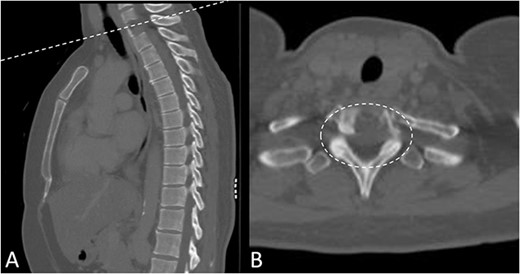

Preoperative magnetic resonance imaging (MRI) and preoperative CT scans helped determine Tokuhashi, Tomita and ESCC scores, which was vital to plan treatment for this patient (Figs 1 and 2). The occurrence of the lesion occurring in T2 indicated an anterior approach. This would be safer than a posterior approach as the ESCC grade of 2 made it surgically challenging to resect tumour and lay instrumentation around the spinal cord. An anterior approach also avoids cervico–thoracic junction fusion.

Preoperative MRI Scan December 2019. (A) Sagittal view of oligometastatic lesion at T2 vertebral body. (B) ESCC grade 2 determined as there is spinal cord compression, but with cerebrospinal fluid visible around the cord.